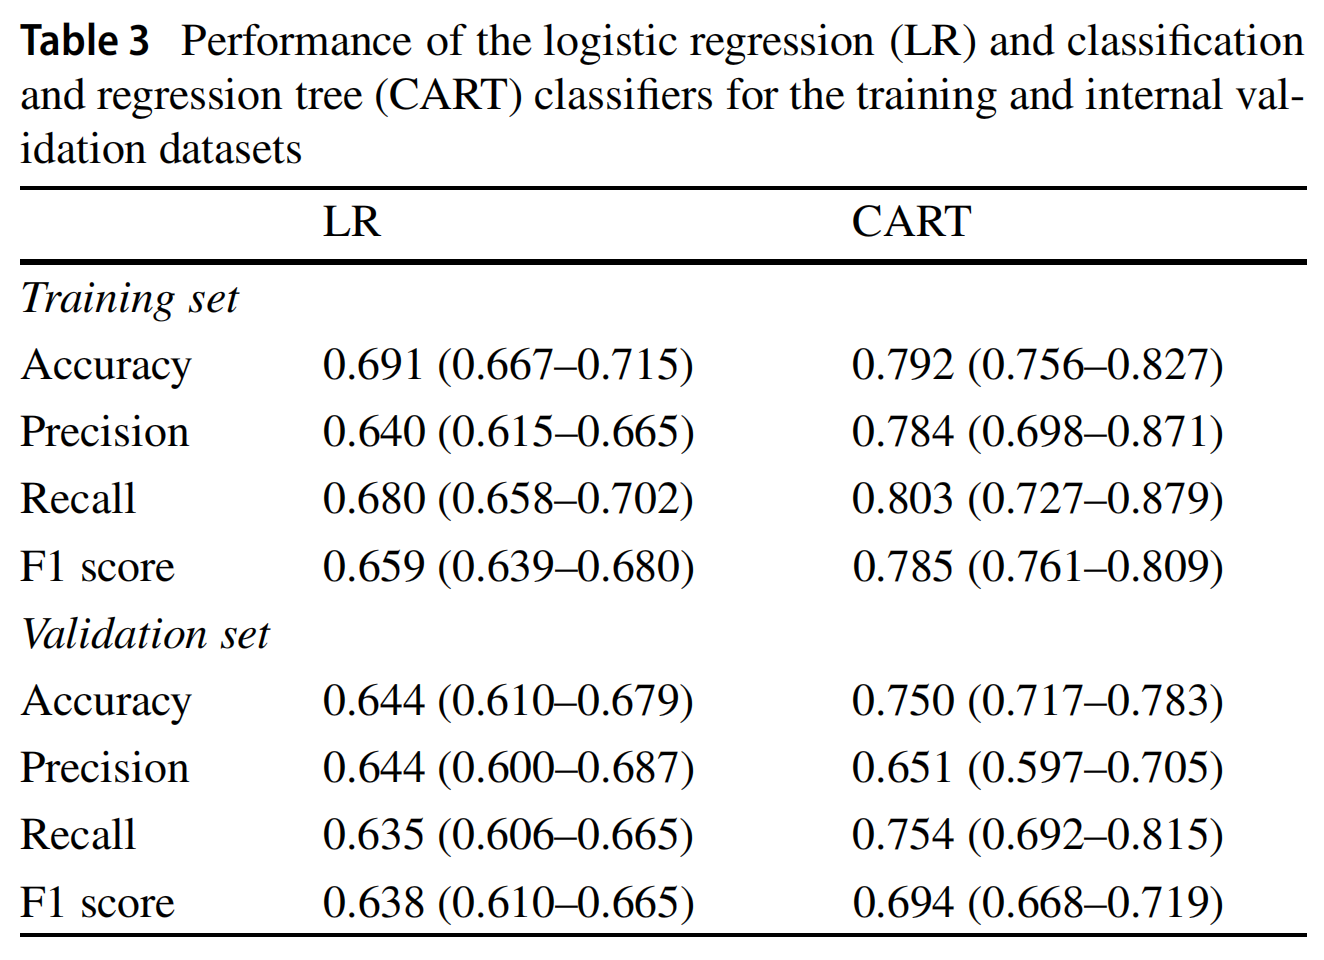

3-3:机器学习模型

LR和CART模型的分类性能在表3中报告了训练和内部验证数据集。CART分类器表现最佳,准确度、精确度、召回率和F1分数分别为79.2%、78.4%、80.3%和78.5%。

两个模型的接收器操作特性(ROC)曲线交叉验证结果在图3中展示。LR和CART模型的曲线下面积(AUC)分别为0.707(95% CI: 0.633–0.817)和0.753(95% CI: 0.675–0.836)。

使用这四个顶级特征,我们训练和评估了两个机器学习模型,使用LR和CART分析方法。最佳的诊断性能是由CART分类器实现的,其在训练集和评估集中的准确度、精确度和召回率分别为0.792、0.784和0.803。获得的CART模型具有明显的优势,即易于解释,与机器学习或深度学习的其他方法不同。我们使用四个放射组学协变量,通过九个节点和三个深度级别构建了CART模型,以产生一个直接和紧凑的决策树。CART分析选择SVR大于0.383的病变与完全缓解相关。随后,偏度和相关性在提高病变分类率方面发挥了重要作用,高偏度和低相关值有利于完全缓解。